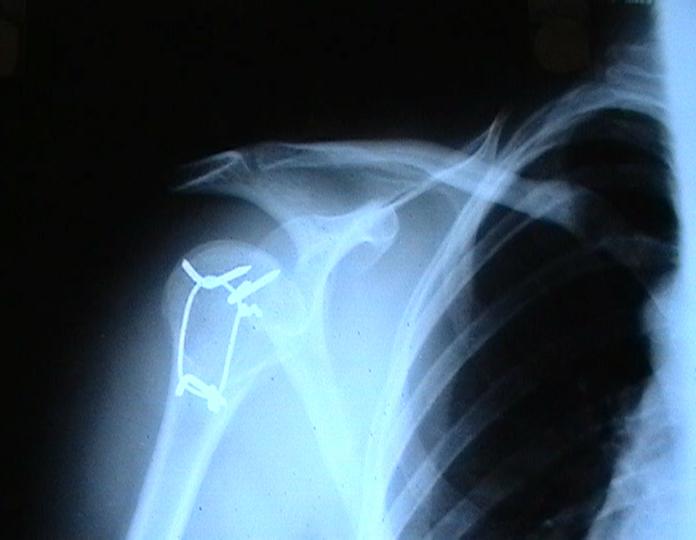

Мужчина 25 лет 16 августа 2002 г. в автоаварии получил перелом шейки плеча (снимок 1); 5 сентября в городской больнице выполнен остеосинтез пластинкой (снимок 2).К настоящему времени попал к нам на разработку ввиду выраженной контрактуры плечевого сустава. В течение последнего месяца беспокоят умеренные боли в области плечевого сустава, усиливающиеся при разработке, еще и торчит край пластинки. Нынешняя рентгенологическаякартина на снимках 3 и 4. Головка плеча уменьшается, сращение сомнительное.Кроме удаления пластинки, что еще на сегодня целесообразно сделать?Заранее спасибо.

Переломовывих плеча сложная проблема и технически не уверен как для коллег, но для меня сколько я не встречался, технически сложно *вытянуть* вывихнутую головку из-под впадины. Последнее время не применяю пластины для фиксации перелома, а использую спицы и проволочную петлю (тем более часто и густо спонгиозные винты не держатся в головке прочно).